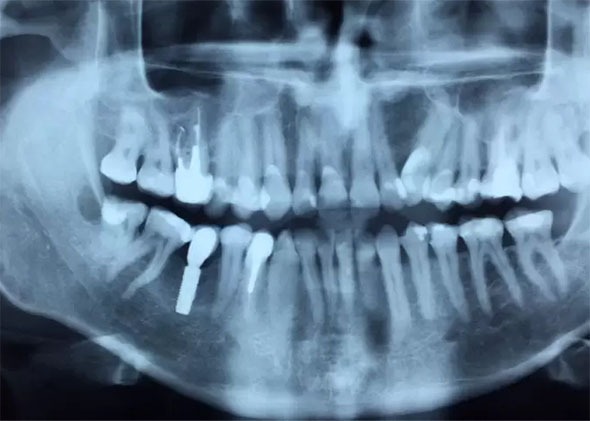

Panoramic X-ray (so-called panorama):

3D image taken with CBCT technology (tomography):